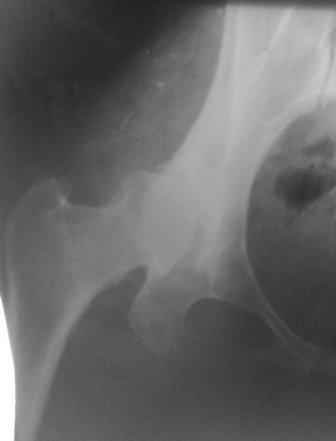

При определении показаний к м/в остеотомии учитываем не только функциональное состояние, но анатомическую форму сустава. Например, при той форме, что на картинке в вашем письме (мелкая впадина,уже не сферичная головка)НИИТО вполне обосновано предлагает ТЭП. Варизирующая остеотомия в "чистом виде" усилит конфликт в опорной зоне сустава. Если очень "настоятельно просит" - экстензия с наружной ротацией по R.Bombelli. То есть на открытом суставе бедро согнуть и ротировать внутрь до покрытия головки впадиной. Сформировать канал через шейку в головку с тем расчетом, что после м/в распила бедро нужно вывести в функциональное положение. Фиксировать 90 град. медиализирующей ортопедической пластиной с клинком. Но выздоровления не обещать, покрытие головки малое, длительного эффекта не будет. Нужна периацетабулярная остеотомия или пластика крыши, но это другая сложность и другая травматичность. Необходимость ТЭП оттянете лет на 10 в лучшем случае. Надо учитывать, что в этом случае ТЭП операция не первая, это увеличивает инфекц. риски и снижает функциональный результат для сустава. Я бы рекомендовал трость с противоположной стороны, ЛФК на приведение, чтобы подрос оссификат крыши и сформировались оссификаты головки. При нормотрофическом типе поражения можно будет провести вальгизирующую остеотомию, эффект которой более длительный или больная за это время найдет возможности приобретения ЭП.

Данный сустав в начальной стадии разрушения, но все-таки я бы сделал обзорный таз и отдельные снимки сустава в 30 градусной абдукции и аддукции. Также снимки с внутренней и наружной ротацией для оценки состояния головки бедра.

Представляю Р-снимки: обзорная, с отведением и с приведением.

Глубокоуважаемый Абдурашид. Здесь нет снимка с отведением. Если Вы сами сходили в рентгенкабинет и лично отвели пораженную конечность максимально возможно, а также дали максимально возможную внутреннюю ротацию-это одно!!!! Значит у пациентки тяжелейшая приводящая контрактура тазобедренного сустава!! И необходимо разобраться-миогенная или артрогенная? Если же Вы просто назначили указанный снимок и доверили произвести укладку рентгентехнику-это другое!!! Одному богу известно, что она делала, ведь на р-снимке отведения нет!

Все предыдущие корреспонденты предлагают вам достаточно простую вещь-смоделировать предлагаемую Вами операцию (т.е. дать отведение и внутреннюю ротацию) и посмотреть, как изменятся соотношения в суставе. Не обижайтесь, но судя по представлению клинического случая угловые величины, характеризующие пространственные соотношения в тазобедренном суставе, ваши рентгенологи не считают.

Глубокоуважаемый Игорь Владимирович! Признаюсь допустил ошибку, из-за напряженности работы и нехватки времени, когда повторно внимательно посмотрел все понял и не успел исправить ошибку до Вашего поста, конечно скошенность крыши в пределах 40гр,часть головки кнаружи линии Омбредана-Перкинса , облитерация дна вертлужной впадины и т.д.-это ДМВБ.